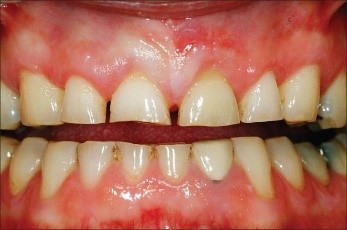

Tanda-Tanda Erosi Gigi

Anda mungkin mengalami erosi gigi jika Anda memperhatikan tanda-tanda berikut:

• Perubahan Warna: Gigi mungkin terlihat lebih kuning karena enamel terkikis dan dentin yang berwarna lebih gelap terpapar.

• Sensitivitas: Gigi mungkin menjadi lebih sensitif terhadap suhu panas, dingin, atau makanan dan minuman manis.

• Gigi Lebih Halus atau Tipis: Enamel yang terkikis dapat membuat gigi terasa lebih halus dan terlihat lebih tipis atau transparan di ujungnya.manis.